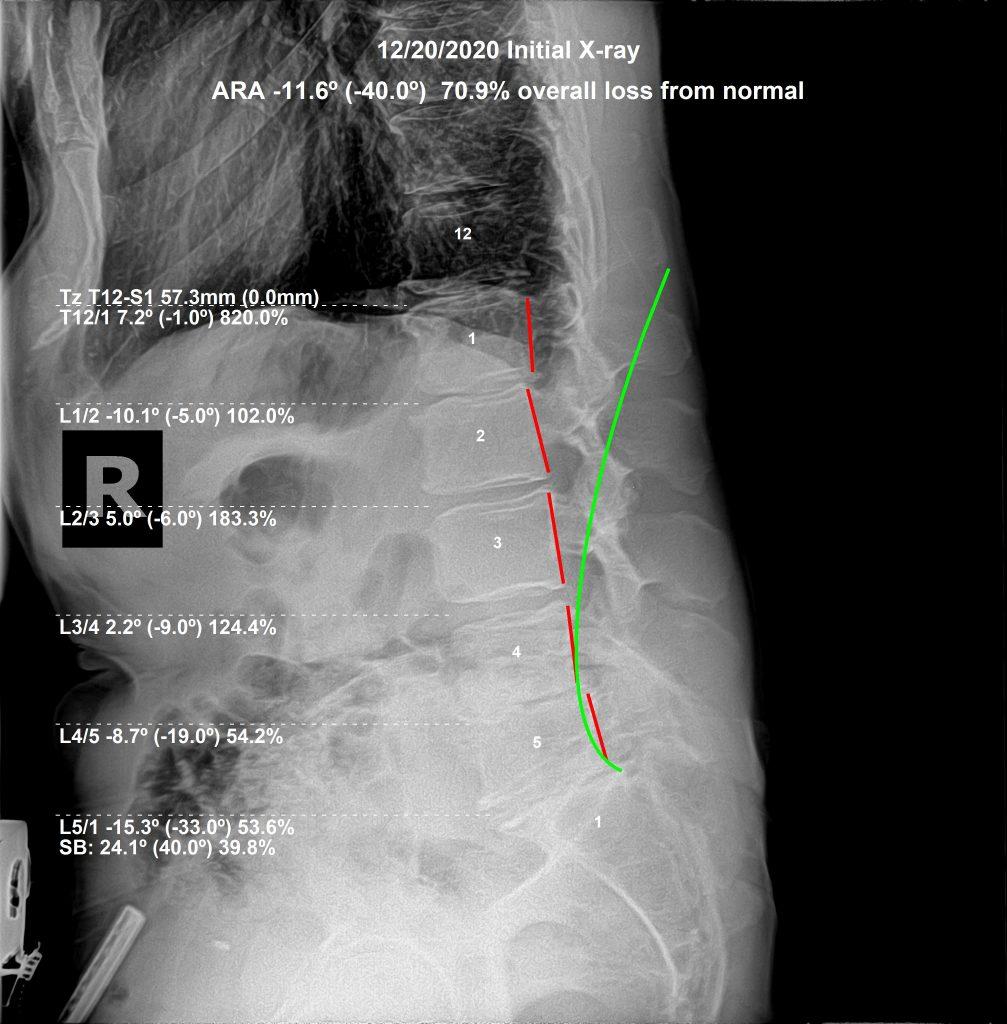

Dr. Rochet evaluates sciatica through neurological testing, orthopedic examination, and lumbar X-rays. These images reveal the exact vertebral positions, disc spaces, and structural alignment of the lumbar spine — identifying the specific subluxation level creating the nerve compression.

This precision matters. A subluxation at L4–L5 produces different nerve distribution than one at L5–S1. The correction is different. Applying the right correction to the right segment — based on X-ray findings rather than symptom location alone — produces more consistent structural outcomes.

As the subluxation reduces and the spine begins to hold, visit frequency decreases. Progress X-rays are taken at re-examination. The goal is not to gauge how you feel — it is to see whether the spine has moved structurally. How a patient feels on a given day tells you something. What the X-ray shows tells you more.

Some patients notice meaningful change within the first few weeks. Others — those with long-standing subluxation and disc degeneration — see more gradual structural improvement over months. The timeline varies. The method does not: correct what is subluxated, track structural change on X-ray, and adjust the care plan based on what the spine is actually doing.

This case involved severe sciatica due to chronic vertebral subluxation, significant degeneration, and disc involvement. His medical doctors recommended spinal surgery. He crawled into our office asking if chiropractic could help.

For a man in his 70s, expectations for meaningful spinal correction were realistically low. We followed subluxation-based adjusting principles and performed McKenzie Disc protocols. After 6 months of corrective care: